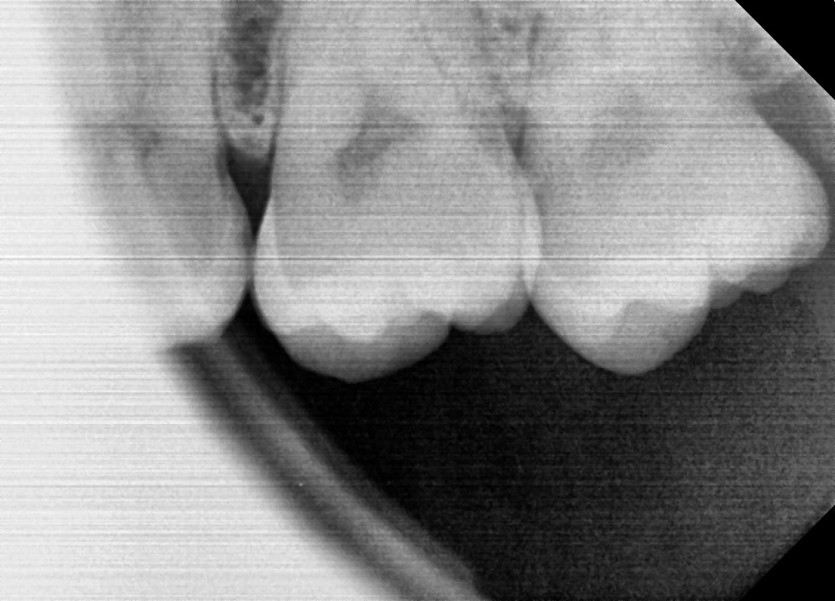

#28,38 사랑니 발치

구강외과 전문의가 당일 발치했습니다.